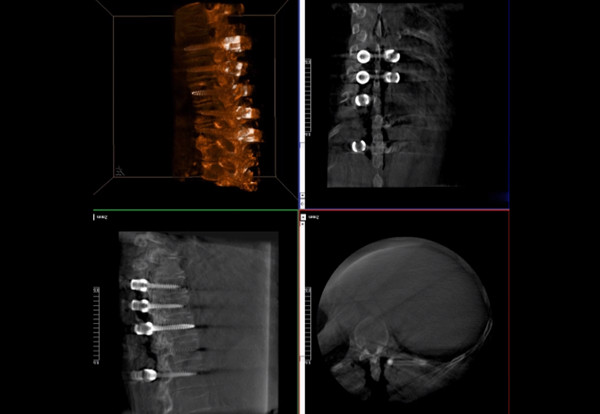

三維影像檢驗螺釘植入效果

一臺C形臂

二維三維影像 皆能完好呈現

使用普愛醫療術中三維導航C臂進行透視,根據透視影像引導確認責任間盤、規劃手術方案,充分暴露骨組織,并通過專業器械切除椎板,暴露神經及椎管;在C形臂的引導下,確定責任間盤上下椎體椎弓根位置,制定進針點及進針方向,沿椎弓根方向植入脊柱螺釘進行固定;放入椎間融合器,加固螺釘。最后再進行C形臂透視,確認手術的完成效果。

手術效果確認